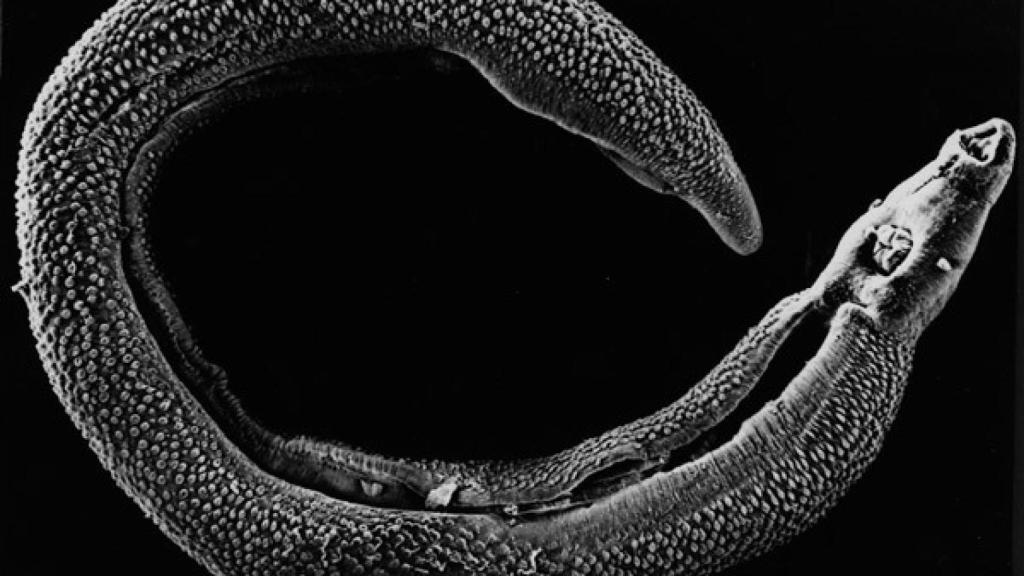

La esquistosomiasis es una enfermedad causada por un platelminto del género Schistosoma que parasita principalmente a los humanos, pudiendo hospedarse en las venas pélvicas, causando lesiones en los aparatos genital y urinario, o en el intestino. El parásito no es ninguna broma, ya que según datos de la OMS, cada año más de 230 millones de personas tiene que ser tratadas, afectando a 77 países, concentrándose el 90% de los afectados en África y siendo las personas en contacto con aguas infestadas las más vulnerables de ser parasitadas, especialmente los niños.

El equipo de investigación llevaba años trabajando con otros tipos de platelmintos, las planarias. Este animal, cuando es adulto, posee un número limitado de células madre, llamadas neoblastos, que regeneran partes del cuerpo que han sido perdidas. Por su gran similitud, pensaron que tal vez el parásito humano Schistosoma mansoni pudiera tener también células equivalentes a las de la planaria y ser estas células las responsables de su longevidad.

Tras muchos análisis y pruebas de laboratorio, marcaron con un fluorescente un tipo de células “sospechosas” de ser células madre por su comportamiento y tras realizar pruebas en ratones se pudo demostrar que efectivamente, eran células madre. Por otro lado, los científicos apuntan que el hecho de haber encontrado células madre en el parásito no tiene por qué ser la única razón de su longevidad, pero sí que es un factor de gran peso. Hay que seguir investigando el papel de éstas células y observar como los huéspedes estimulamos a las células del parásito para que se divida.